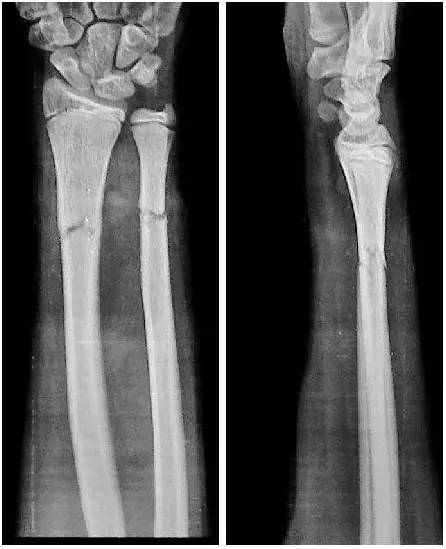

宝宝13个月,右侧尺桡骨远端骨折,对位对线可是

3岁孩子右手桡骨远端骨折 五天后复查对位对线